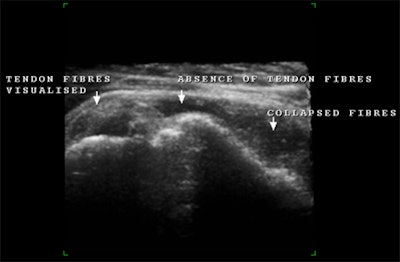

![]() |

| Above and below, post-traumatic multiplanar and enlarged 3D reconstruction of the supraspinatus tendon with small marginal tears that were better depicted using 3D reconstruction. |

| 3D representation of a post-traumatic rupture of the supraspinatus tendon. |